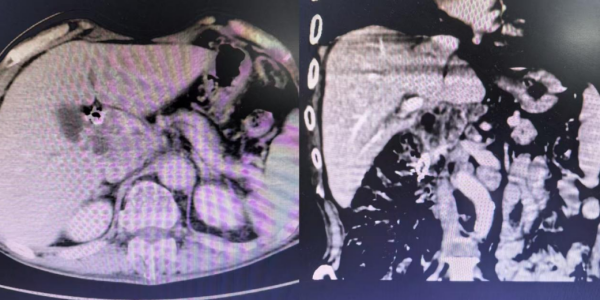

整个手术过程一气呵成,成功开通了梗阻的胆道。手术创口小,患者术后恢复快,全身皮肤及巩膜黄染明显消退,食欲显著好转,精神状态恢复,体重也有所增加,日常生活实现自理。复查CT显示胆道梗阻解除,胆道支架及碘125粒子条位置良好。

胆道支架植入后胆道梗阻解除

胆总管支架术后改变,肝内胆管无明显扩张